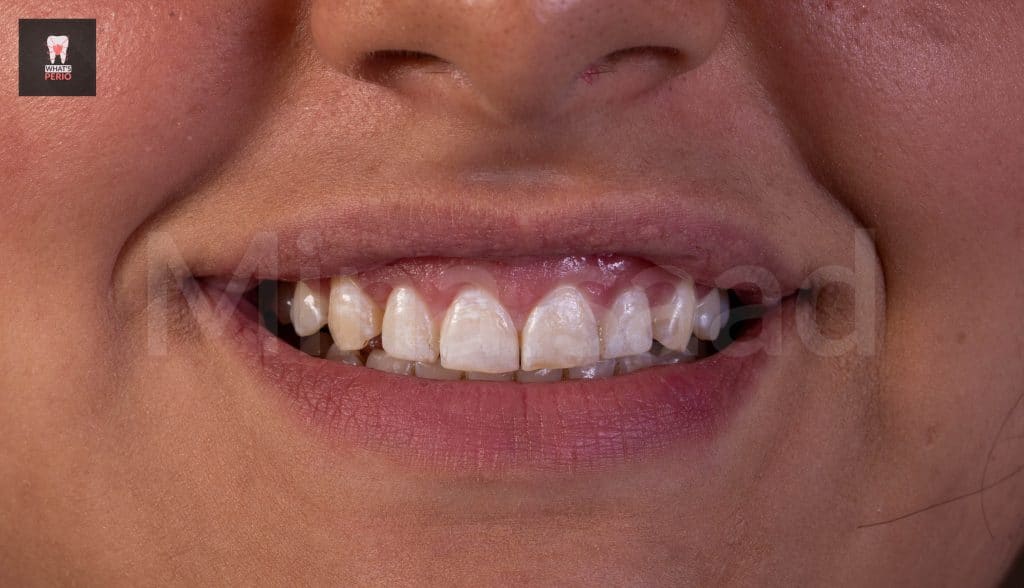

-The patient is recalled after 4 weeks & it was observed that the gummy smile was decreased & the patient was very satisfied with the result & decided to postpone the 2nd step.